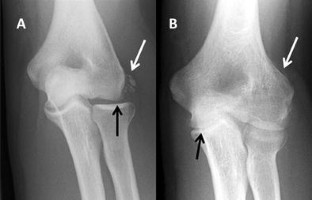

Fig. 1